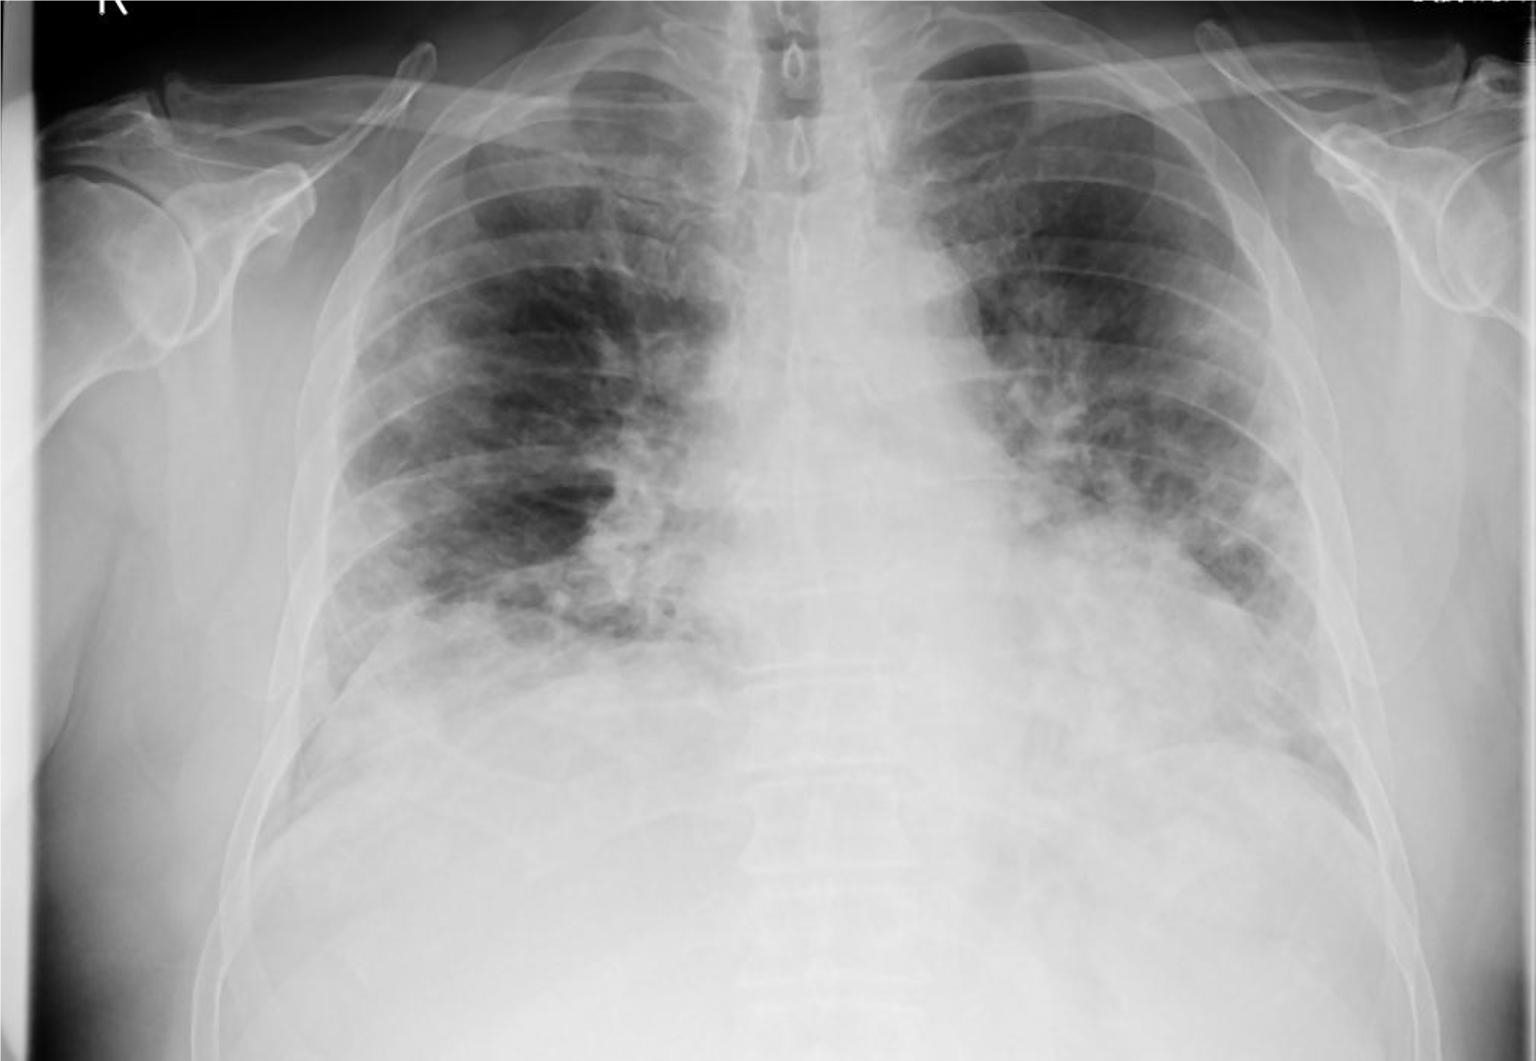

Prof. Dr. Alexander Jesser, betreute gemeinsam mit seinem Mitarbeiter Roman Radtke die Studentin bei ihrer vielversprechenden Forschungsarbeit. Prof. Dr. Jesser erläutert: „Bei einer Erkrankung der Lunge ist das betroffene Gewebe meist weniger transparent für die Röntgenstrahlung und kann durch seine Form und Abgrenzung Aufschluss geben, um welche Art der Krankheit es sich handelt. Eine Covid-19-Erkrankung zeigt meist milchglasartige Veränderungen in beiden Lungenflügeln. Ist eine Erkrankung der Lunge durch eine Infektion mit Bakterien erfolgt, ist mehrheitlich nur ein Flügel der Lunge verändert. Eine gleichmäßige Ausbreitung über alle Bereiche der Lunge ist dabei also ein Hinweis auf eine Covid-19 Infektion.“

Zur automatisierten Auswertung werden die Aufnahmen in einen Standard-PC eingelesen und mit einer speziellen mathematischen Operation der Kontrast erhöht - ein Vorteil bei qualitativ schlechten Aufnahmen, die mit älteren Röntgenanlagen entstehen. Die Software erstellt neben einem Falschfarbenbild, das die Auswertung vereinfachen kann, ein Binärbild, auf welchem sich bereits die Umrisse der Lunge, sowie Spuren von geschädigtem Gewebe erkennen lassen. Durch einen weiteren Algorithmus werden die im Binärbild vorhandenen Kanten und Grenzen der einzelnen Bereiche ermittelt. Die Software kann durch weitere Berechnungen Flächen- und Symmetriebetrachtungen vollziehen und anhand dieser mit großer Wahrscheinlichkeit zwischen bakterieller- oder viraler Lungenentzündungen unterscheiden.